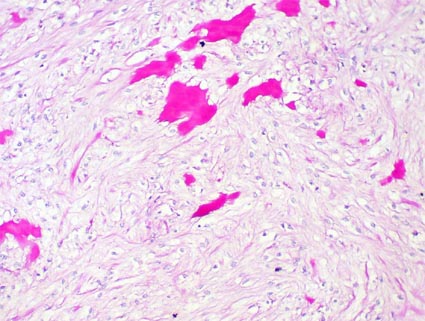

Macroscópicamente son nódulos bien definidos, esféricos, grisáceos, pálidos, de consistencia firme y generalmente localizados en la porción media de la médula, miden 2-5 mm. Microscópicamente son poco celulares, no encapsulados, compuestos de células fusiformes o estrelladas en medio de un estroma similar al de la médula renal; podemos ver bandas de tejido fibroso laxo y, algunas veces, material amiloide. Con frecuencia hay túbulos medulares atrapados en la peroferia de la lesión. [Imagen micro (link)] [Imagen micro (link)]

Figura 28. Lesión poco celular, con células de aspecto fibroblástico, sin atipia, en medio de un estroma fibrilar y, en muchos casos, con bandas de tejido hialino, eosinofílico como puede verse en ambas imágenes. No suelen identificarse mitosis. La lesión es bien definida pero no encapsulada. (H&E, izquierda, X200; derecha, X400).